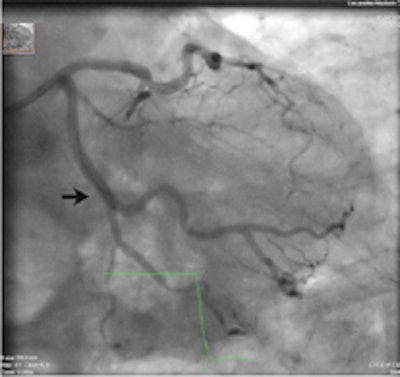

A 64-year-old patient with carotid stenosis. Top left: Coronary CT angiography image. White arrow points to a soft plaque in the midcircumflex artery, with stenosis of the lumen. Calcium score was 64. Top right: Short-axis image of the adenosine perfusion MRI examination. White arrow points to a perfusion defect in the posterolateral wall, during stress. The perfusion defect was not present in the rest series, thus indicating inducible ischemia. Bottom left: Invasive coronary angiography image of the left coronary arteries. Black arrow points to a significant stenosis, corresponding with the location seen on CT. Bottom right: Invasive coronary angiography image after intervention. Good results were achieved after percutaneous coronary intervention with stent placement. All images courtesy of Drs. Rozemarijn Vliegenthart and Martijn den Dekker.Two centers in the Netherlands scanned 115 cardiac-asymptomatic patients age 50 years and older (mean age 65 years; 76% men) with proven aneurismal or stenotic arterial disease with CT, MRI, and sometimes echocardiography as well.